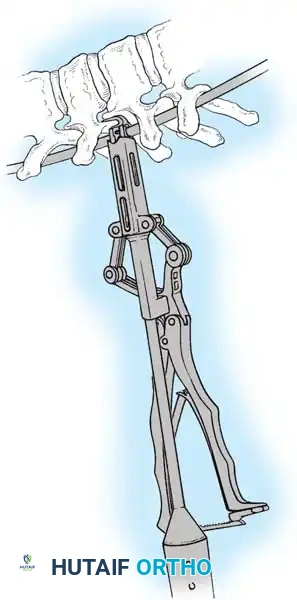

The Hall Technique

The Hall technique offers an alternative method for facet obliteration and grafting, particularly useful in rigid deformities.

Fig. 38-28: The Hall technique of facet fusion, involving sharp excision of the inferior facet and trough creation.

- Sharply amputate the inferior articular facet with a gouge and remove the bone fragment entirely. This exposes the cartilage of the superior facet.

- Remove the exposed cartilage completely with a sharp curet.

- Create a bleeding trough by removing the outer cortex of the superior facet.

- Impact cancellous bone grafts directly into this vascularized trough.

- Complete the procedure with global decortication of the posterior elements.